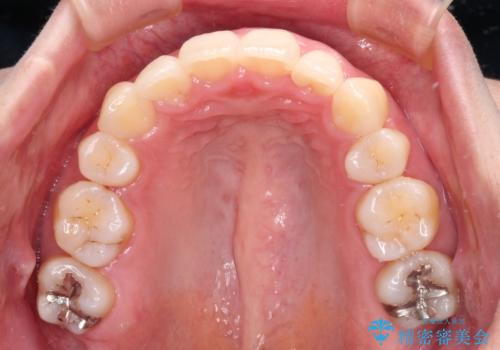

- 抜歯矯正の後戻りで前歯が突出してきていることを気にして来院された患者様です。

口元の突出感を改善するにあたり、抜歯矯正は行うことができないため、奥歯の後方移動とIPR(歯と歯の間を削る)により達成することとしました。

再度後戻りしたときに対応しやすいよう、インビザラインにて矯正治療を行うこととしました。

しっかりと装着時間を守り、ゴムかけにも協力していただいたので、口元を引っ込めることができました。